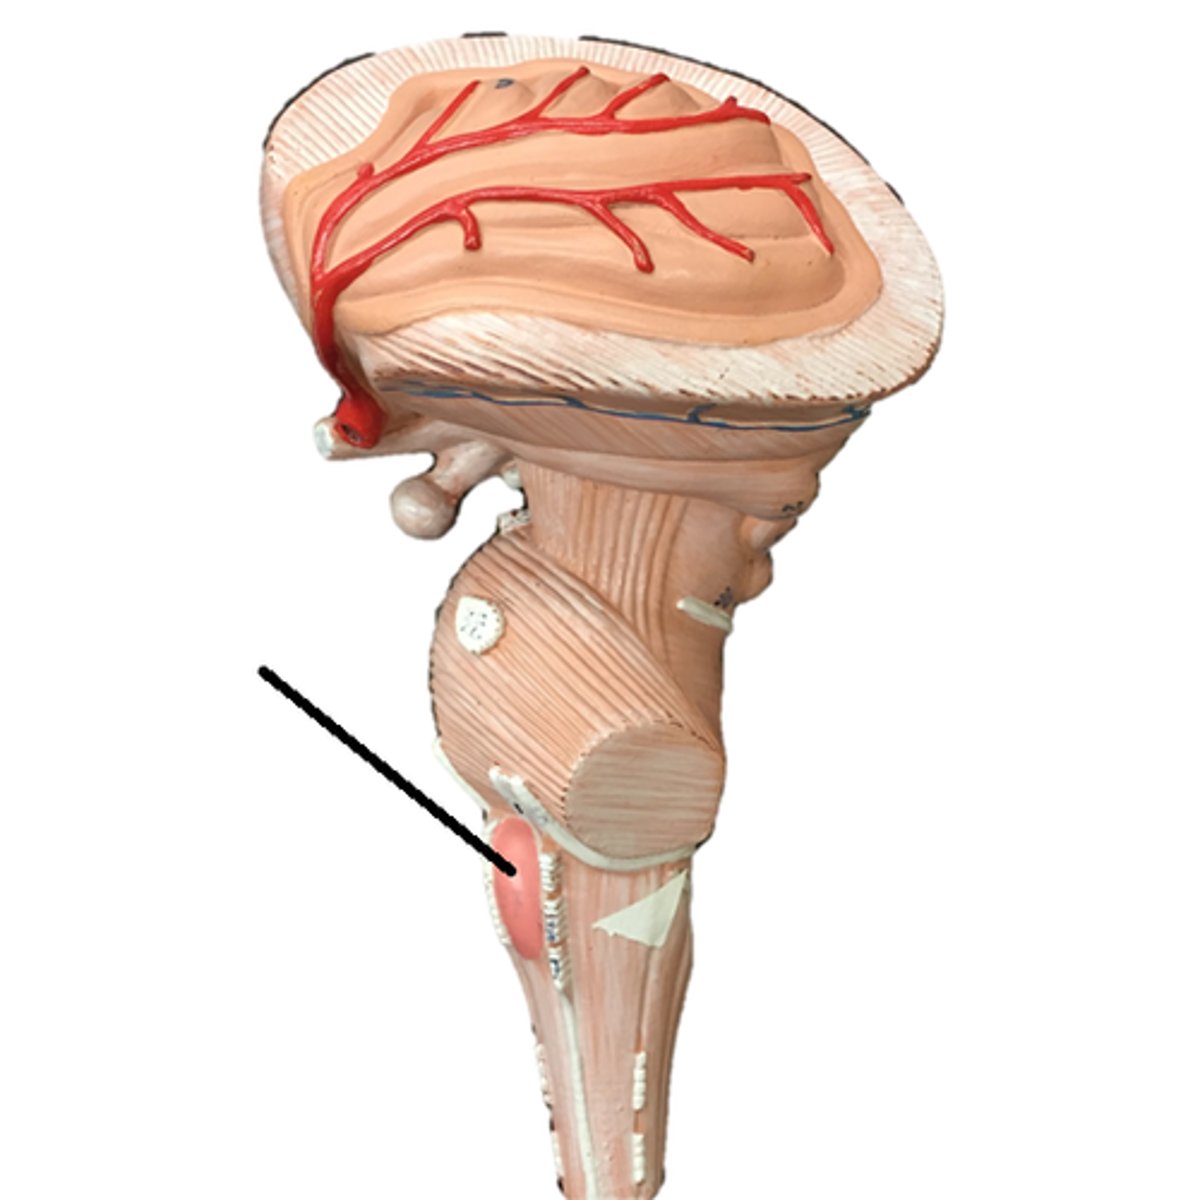

cerebellar peduncles

pons

medulla oblongata

olive